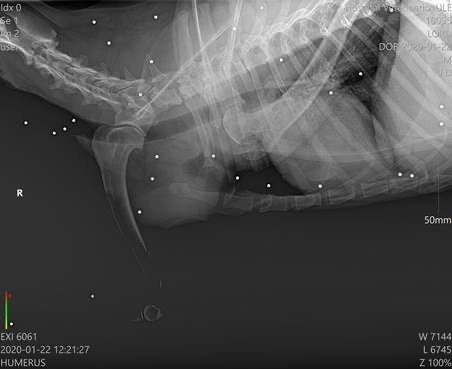

Der kleine Kerl begann zu humpeln und nach weiteren Untersuchungen sowie dem Besuch bei einem Spezialisten, wurde festgestellt, dass er unzählige Schrotkugeln im Körper hat und Arthrose in diversen Gelenken.Lord wird leider zukünftig auf Schmerzmedikamente angewiesen sein.

Der kleine Kerl begann zu humpeln und nach weiteren Untersuchungen sowie dem Besuch bei einem Spezialisten, wurde festgestellt, dass er unzählige Schrotkugeln im Körper hat und Arthrose in diversen Gelenken.